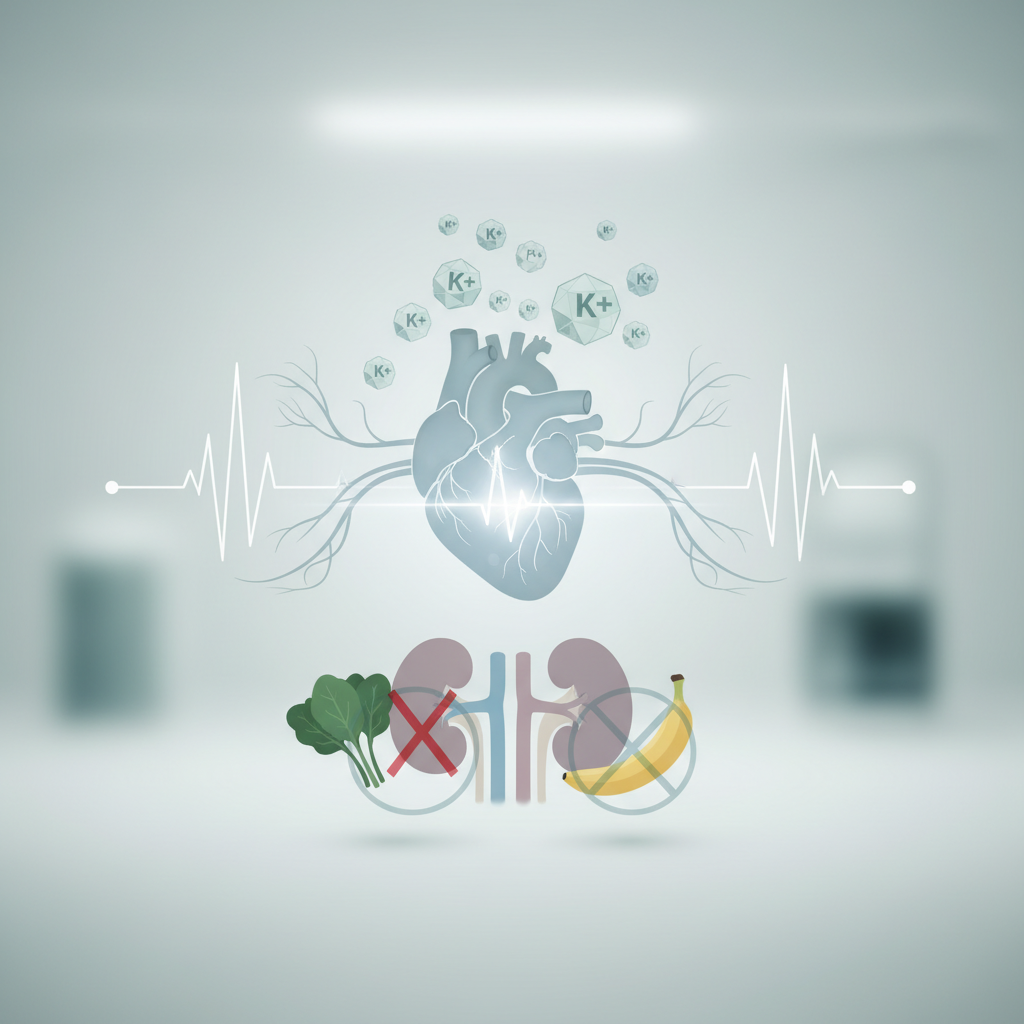

Per daug kalio organizme: požymiai, kurių nevalia ignoruoti

Kalis yra vienas svarbiausių mineralų ir elektrolitų žmogaus organizme, atliekantis esminį vaidmenį užtikrinant sklandžią nervų sistemos veiklą, raumenų susitraukimus ir, svarbiausia, normalų širdies ritmą. Kiekviena […]